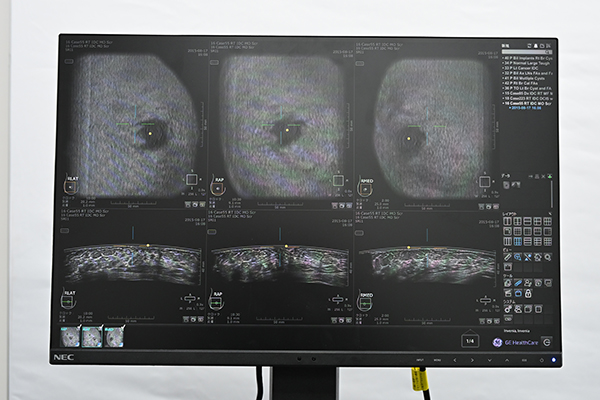

遠隔読影など多様なニーズに応えるワークステーション